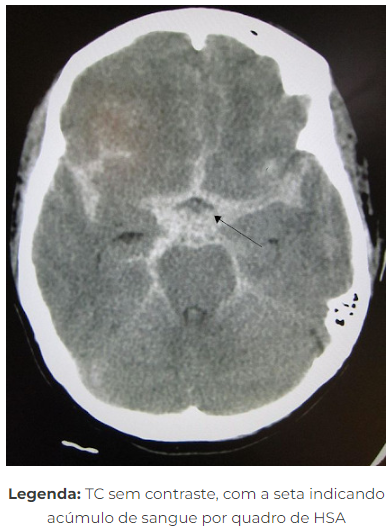

AVC h

- hemorragia subaracnóidea

A

• ruptura aneurismasocular congênito ( 35-5Sa) ou MAV (15 a 30 a)

• cefaleia em trovão + Síncope+ Rigidez de nuca

• TC crânio= Sangue no espaço subarachoide - Se TC normal = punção lombar. (primeiras 12hs= líquor sanguinolento → depois xantocrônico (bilirrubina)